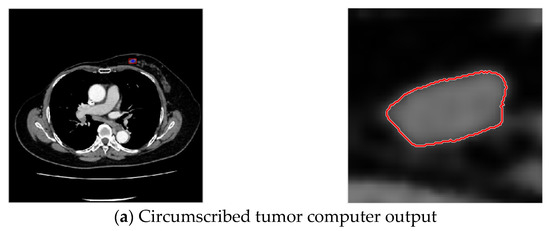

In this study, breast tumor images were divided into three types according to features of their margins [29,30,31], namely, circumscribed tumors, lobulated tumors, and spiculated tumors, as shown in the Figure 1.

Figure 1.

Types of breast cancers.